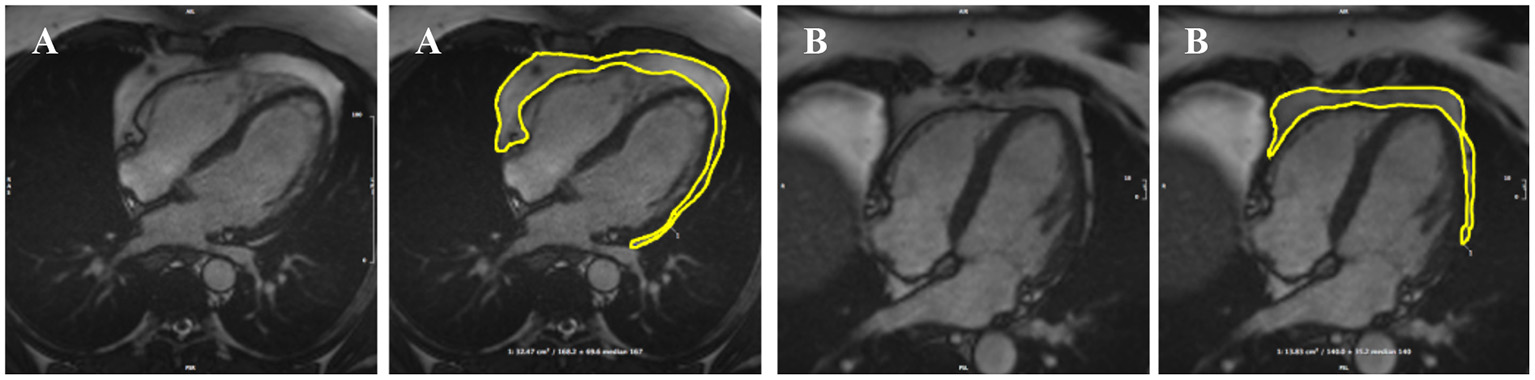

The analysis protocol comprised segmentation of an en bloc PAT area from standard four-chamber cine images (single 2D slice), a universal component of standard CMR studies and one that demonstrates less variability in cut plane positioning compared to other acquisitions (e.g., short axis slices). For consistency, we measured PAT at phase 1 of the imaging cycle (approximately end-diastole). A single contour was drawn to select areas of high signal intensity adjacent to the epicardial surface of the left and right ventricular myocardium, resulting in output of an area measure in cm2 (Figure 1). Areas of high signal intensity over the liver were not included, as this almost always represents adipose tissue below the diaphragm (Figure 1B).

Figure 1. Two examples of PAT contoured in end-diastole on four-chamber bSSFP cine-CMR, performed using CVI42® software according to the established SOP. A single contour was drawn to select areas of high signal intensity adjacent to the epicardial surface of the left and right ventricles, resulting in output of an area measure (A). Areas of high signal intensity over the liver were not included in the PAT measure as this almost always represents adipose tissue below the diaphram (B). bSSFP, balanced steady state free precession; CMR, cardiovascular magnetic resonance; PAT, pericardial adipose tissue; SOP, standard operating procedure. Images reproduced with permission of UK Biobank.